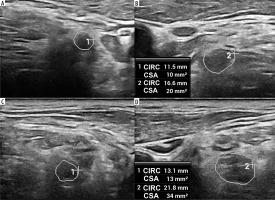

Figure 3

High-resolution ultrasound image of the C5 (A, B) and C6 (C, D) roots with cross sectional area (CSA) measurements in 57-year-old patient with Parsonage-Turner syndrome. Root swelling, reflected by increased CSA and circumference (CIRC) detected on the symptomatic side. Images obtained by author with a 5-20 MHz linear probe of the Mindray Resona I9